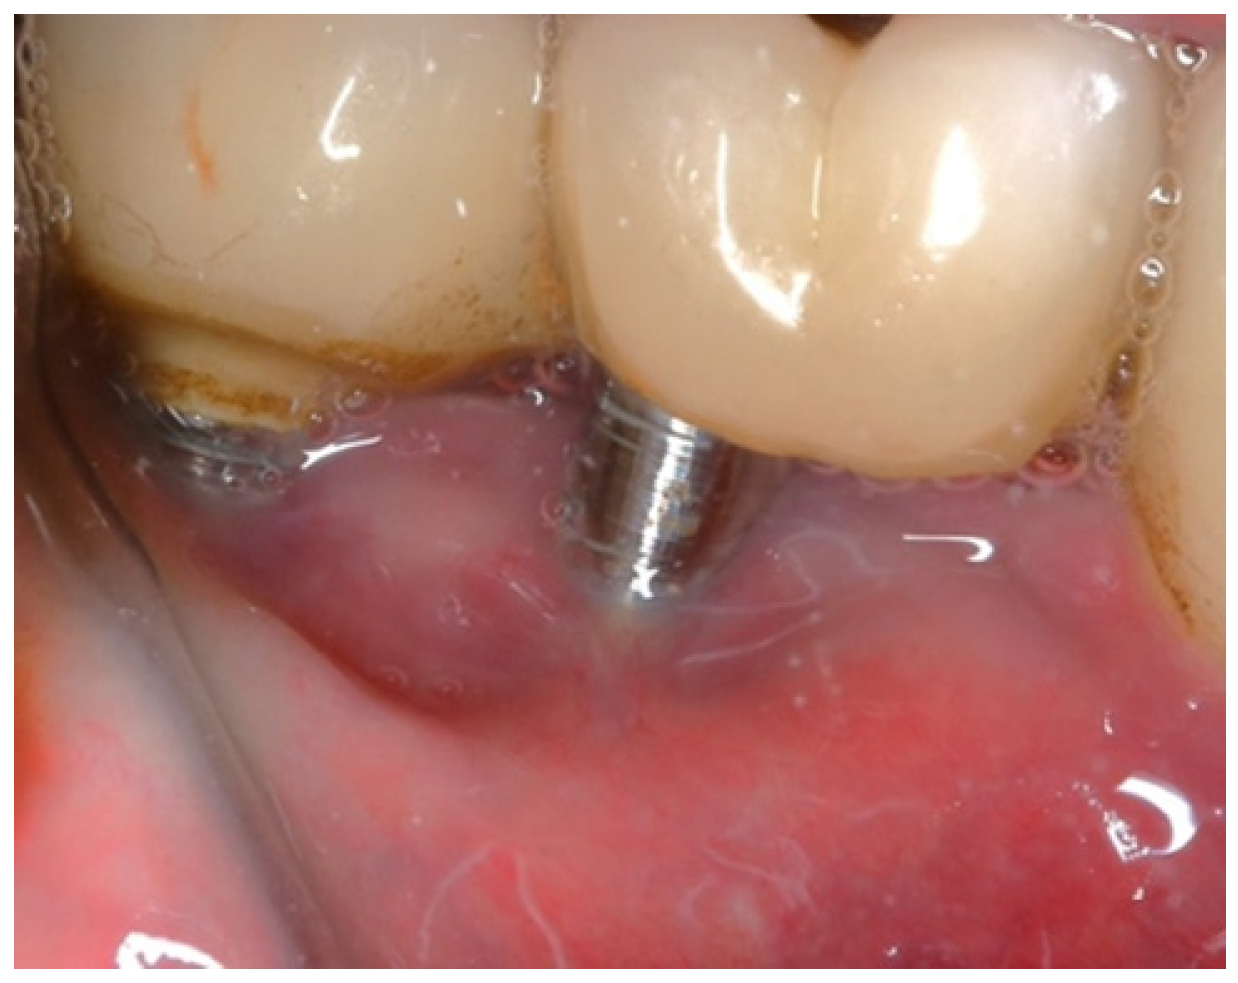

A 75-year-old male patient presented to the private clinic (Tel Aviv-Yafo, Israel) with severe pain, swelling, bad odor, and suppuration localized in the lower right posterior region (Figure 6). The chief complaint indicated discomfort and functional impairment related to that site. The implants placed in the first and second lower right molar region presented severe and vertical bone loss. The patient was a heavy smoker, 2–3 packs/day for 50 years, but quit smoking 5 years ago. Systemically, the patient had diabetes mellitus, controlled with daily insulin (HbA1C between 6% and 7%); osteoporosis, managed with bisphosphonates (via oral, around 2 years); and a cardiovascular condition, requiring anticoagulant therapy (more than 5 years).

The intraoral examination revealed poor oral hygiene, characterized by significant plaque accumulation (over 65% plaque index) along the gingival margins and interdental areas. The periodontal status evidenced a progressive periodontal disease, with bleeding on probing (BoP) over 60%, mainly around all dental implants; peri-implant tissues possessed a high level of inflammatory condition, with localized swelling, high level of BoP, redness, and suppuration at the site of teeth #46 and #47, indicating local acute inflammation. The probing depth (PD) at site implant #46 exceeded 9 mm at both the mesial and distal sites, and at #47, the mesial site had a PD of 7.8mm, while the distal site showed lower bone loss (Figure 7).

Figure 6. Initial clinical assessment of sites #46 and #47.